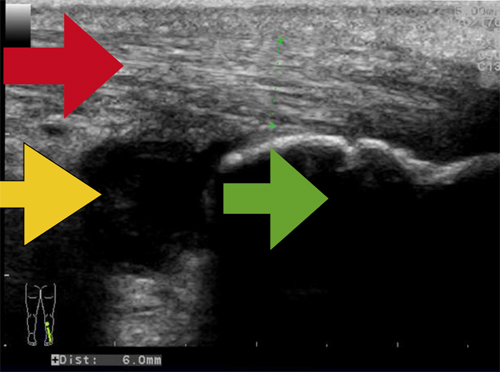

Exempel hälsena

Exempel hälsena  Fråga oss